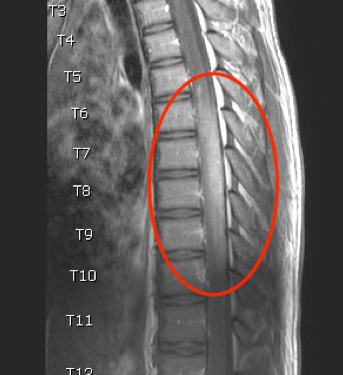

Pediatric spinal glioblastoma is an extremely rare diagnosis with a poor prognosis. Spinal cord tumors comprise less than 1% of pediatric central nervous system tumors, most of which are ependymomas and...

05/23/2018